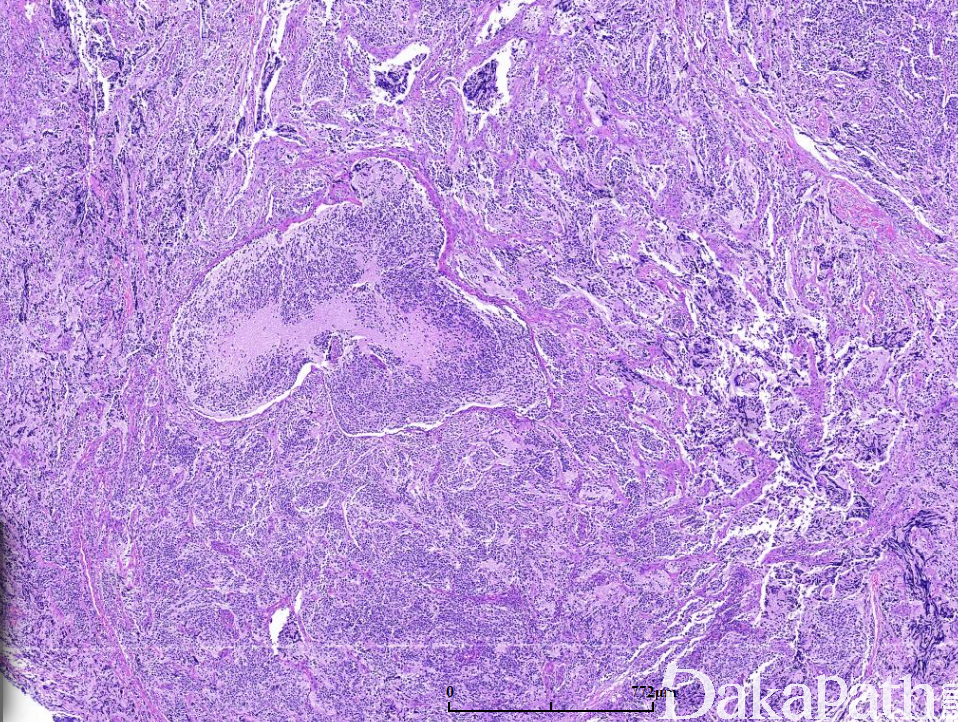

由巢状或小叶状分布的小至中等大神经母细胞所组成,巢或小叶之间为纤细的纤维血管性间隔;

在未分化型的神经母细胞形态学基础上,在局灶区域或明显可见神经纤维网(神经毡)和(或)Homer-Wright 菊形团(约 30%):1 层或数层神经母细胞围绕中央的神经毡性间质呈放射状排列;